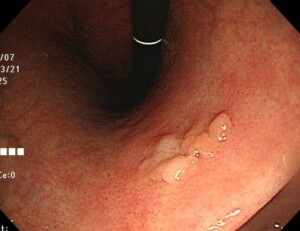

④胃がん

早期胃がんはわずかにへこんでいるか平坦なことが多く、はっきりと盛り上がっていることはあまりありません。胃腺腫かと思ったら胃がんだったということもあります。この症例も早期がんでした。